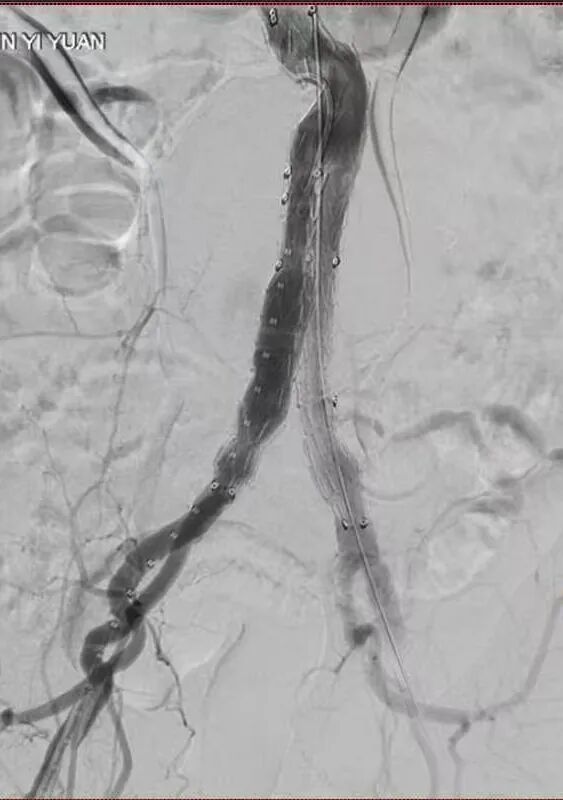

术后影像

介入血管外科团队凭借精湛的技术,在专用DSA机器的引导下,他们如同在微观世界里进行一场精密的“导航”。支架放置的精准度是手术成功的关键。放置过高可能阻塞肾动脉血供,过低则可能影响远端血流。经过精心操作,手术团队成功将覆膜支架定位于理想位置,完全隔绝了动脉瘤,同时保证了重要分支血管的血流通畅。最终,顺利拆除了患者体内的“不定时炸弹”,这场高难度手术最终圆满成功!